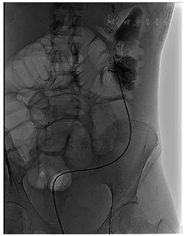

实验室检查:白细胞计数9.2×109/ L,中性粒细胞88.3%,血红蛋白56 g/L,降钙素原124 μg/L,白蛋白22.1 g/L,前白蛋白20 mg/L。消化道道造影提示,经肛门注入造影剂,可见只有直肠中下段显影良好其余结肠显示不清,广泛结肠及直肠炎,回盲部也受累(图1)。经外瘘口注入造影剂,见左盆腔不规则脓腔显影(图2)。骨密度检测提示骨质疏松。